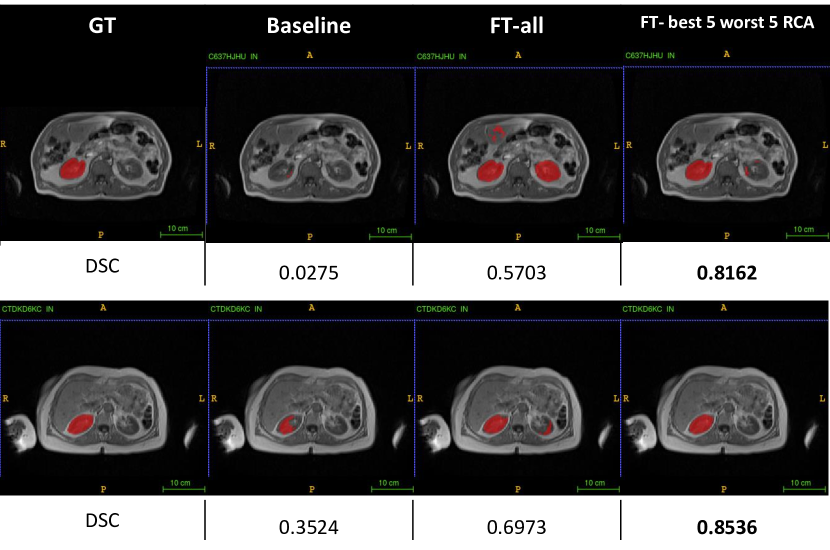

3.4 Fine-tuning in Right Kidney Segmentation

From the three different strategies of DARCA in liver segmentation, we can see that fine-tuning with DARCA gives better results, less time-consuming (compared to training from scratch), and no iterative scheme needed. Also, from the results in liver segmentation (Table 2), combination of best-5 and worst-5 subjects always gives better or similar results than using all of the subjects from domain T, in all strategies. To validate these results, we also explore DARCA-FT in a different task: right kidney segmentation.

Similarly, the best results of right kidney segmentation with fine-tuning are achieved when we combine best-5 and worst-5 subject selection (see Table 4). The result (DSC: 0.716 with RCA selection) is better than when fine-tuning with all of the subjects from T (DSC: 0.658), and similar to when we train from scratch using all target subjects. This means we could cut the processing and annotation time. Figure 5 depicts some examples on how DARCA-FT with combination of best-5 and worst-5 subject selection improves the baseline and gives the best segmentation accuracies.

All of our strategies in DARCA (training from scratch, fine-tuning, and iterative) show a consistent result, combination of best-5 and worst-5 subject selection yields best results. RCA selection of those combined subjects also results in a similar accuracy to the real selection, compared to a bigger gap between RCA and real selection when fine-tuning with only best or worst subject selection.

In this scheme, DARCA shows its potential to leverage the highest and lowest confident subjects, to be incorporated in the domain adaptation process. We demonstrated that DARCA with few labeled data can perform similarly and/or better to full-size labeled target data. In the examples of Figure 4 and Figure 5, DARCA with best-5 and worst-5 subjects show consistent results across different tasks (liver and kidney segmentation).